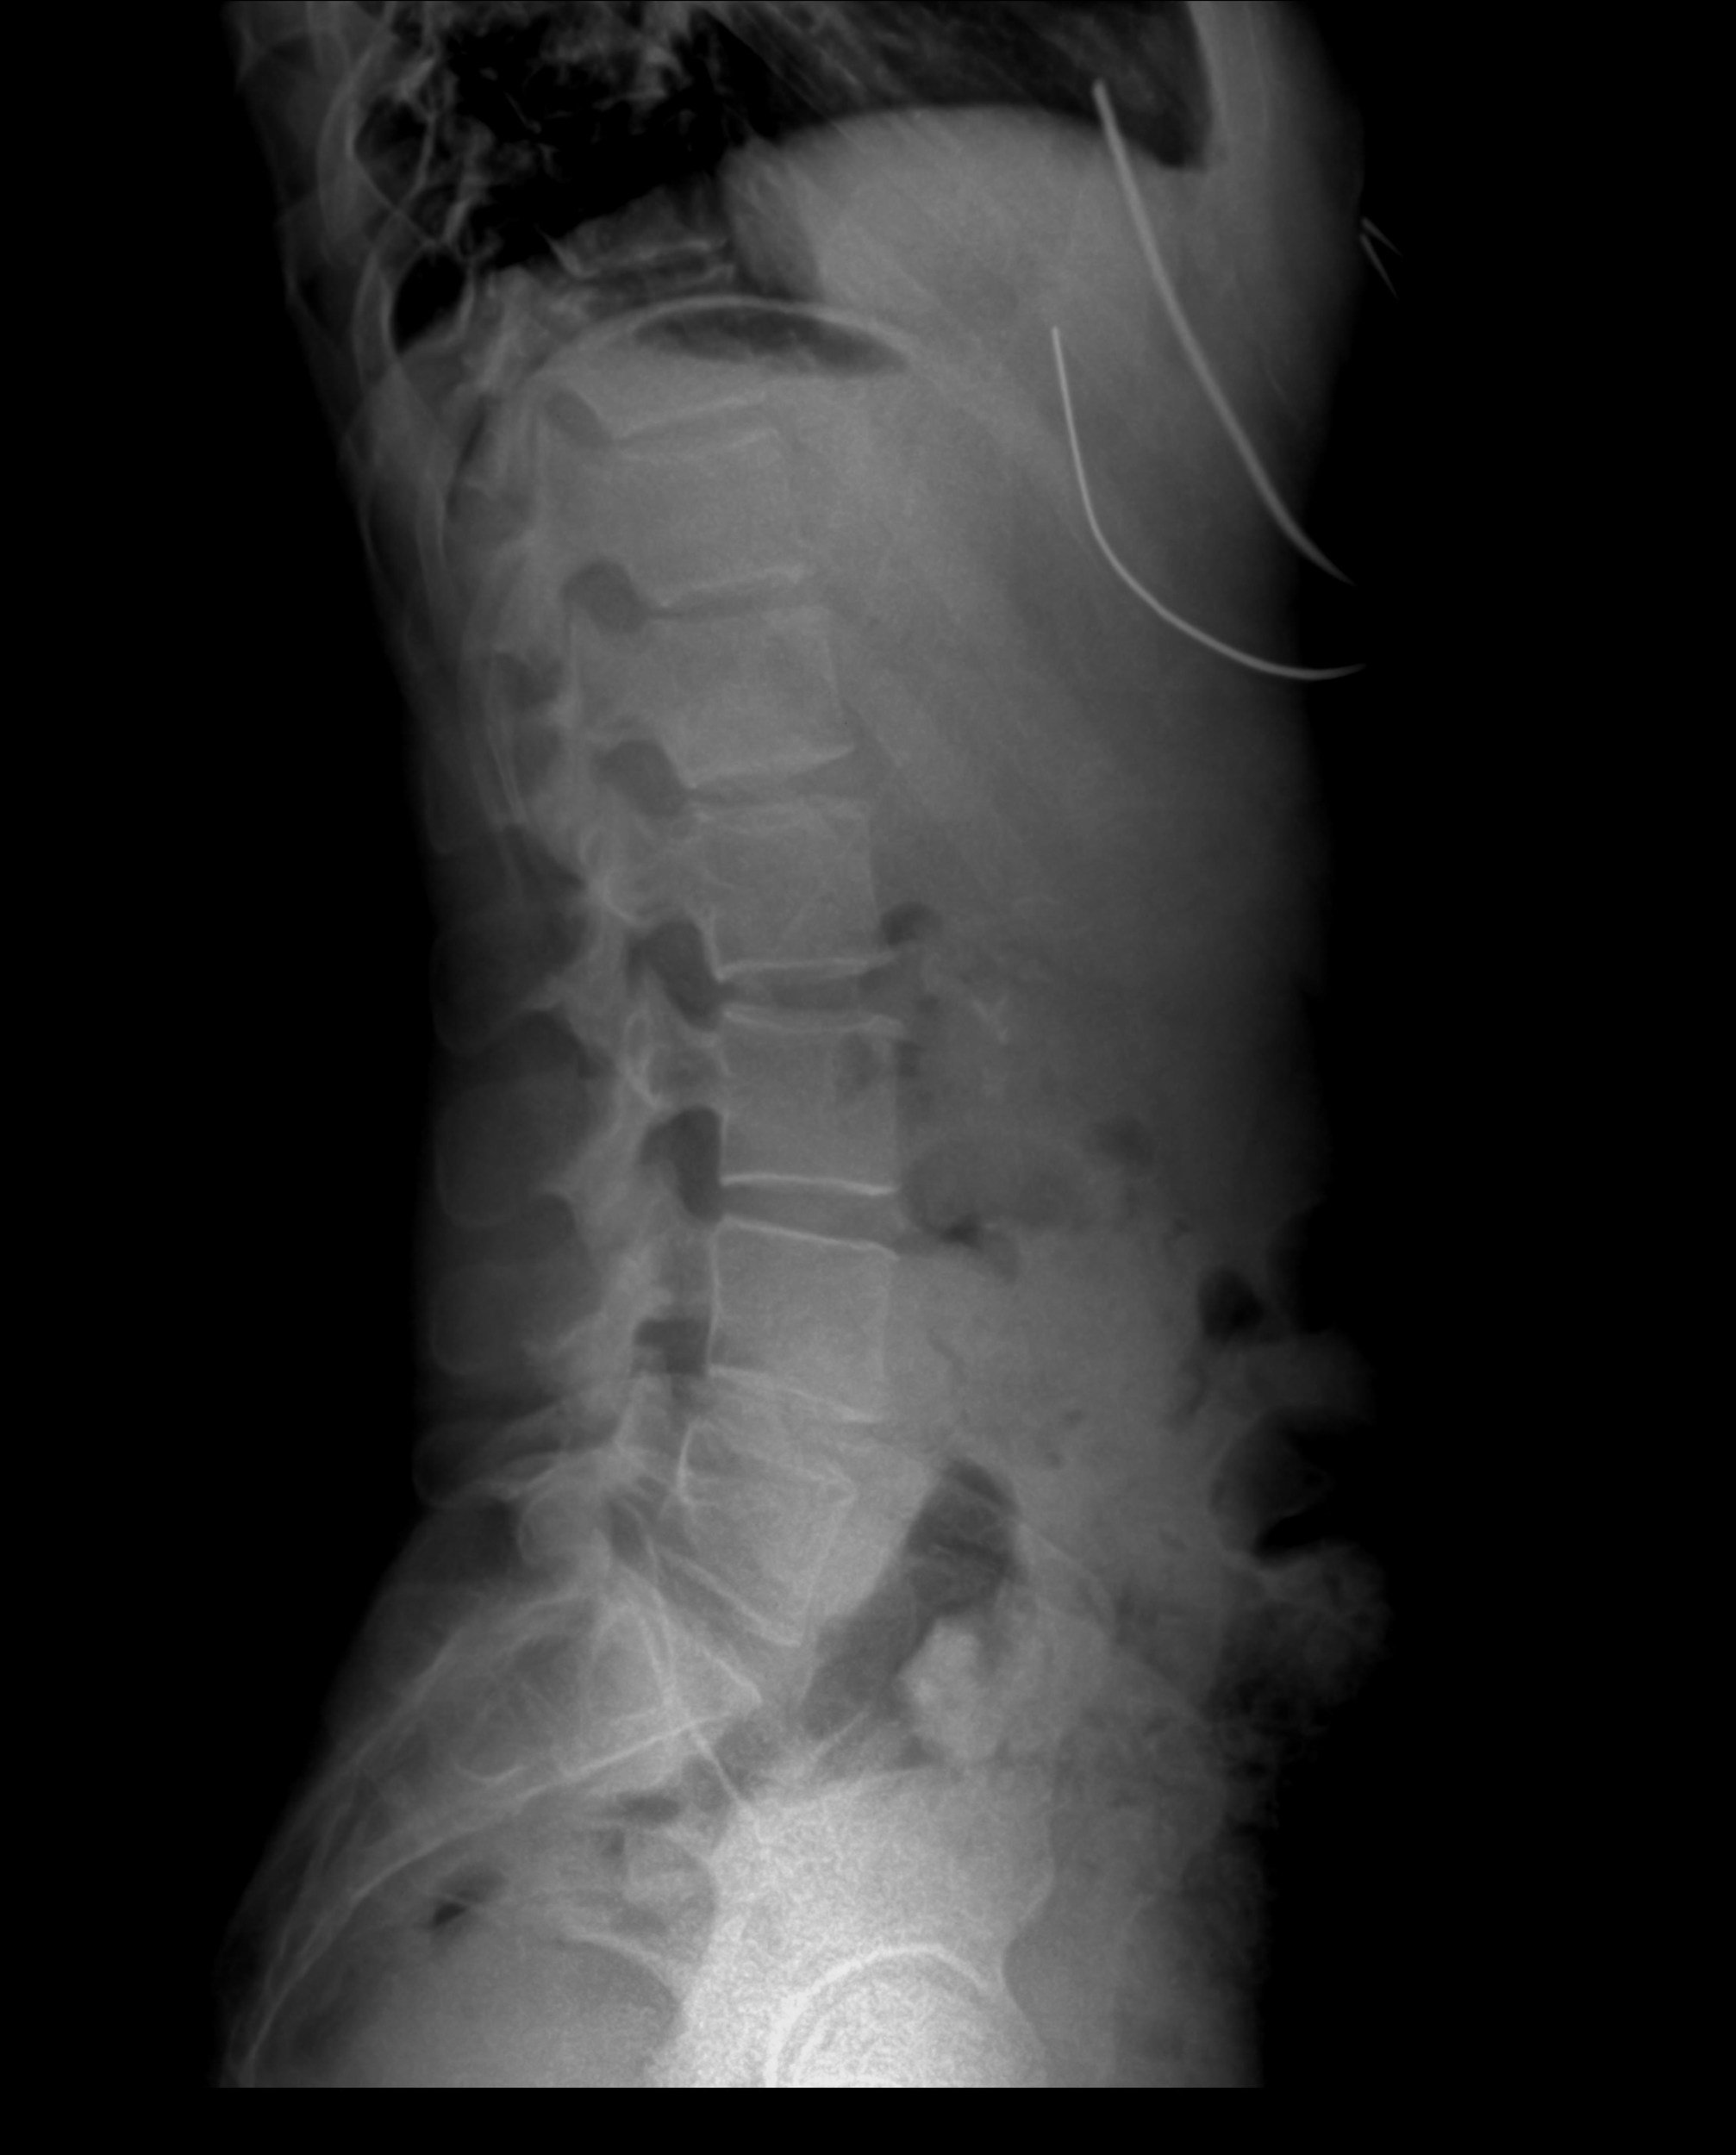

• Spinal cord injuries.